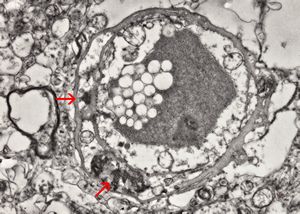

F,50y. | progressive multifocal leukoencephalopathy- viral particles in a glial cell

F,50y. | progressive multifocal leukoencephalopathy- viral particles in a glial cell

F,50y. | progressive multifocal leukoencephalopathy- viral particles in a glial cell